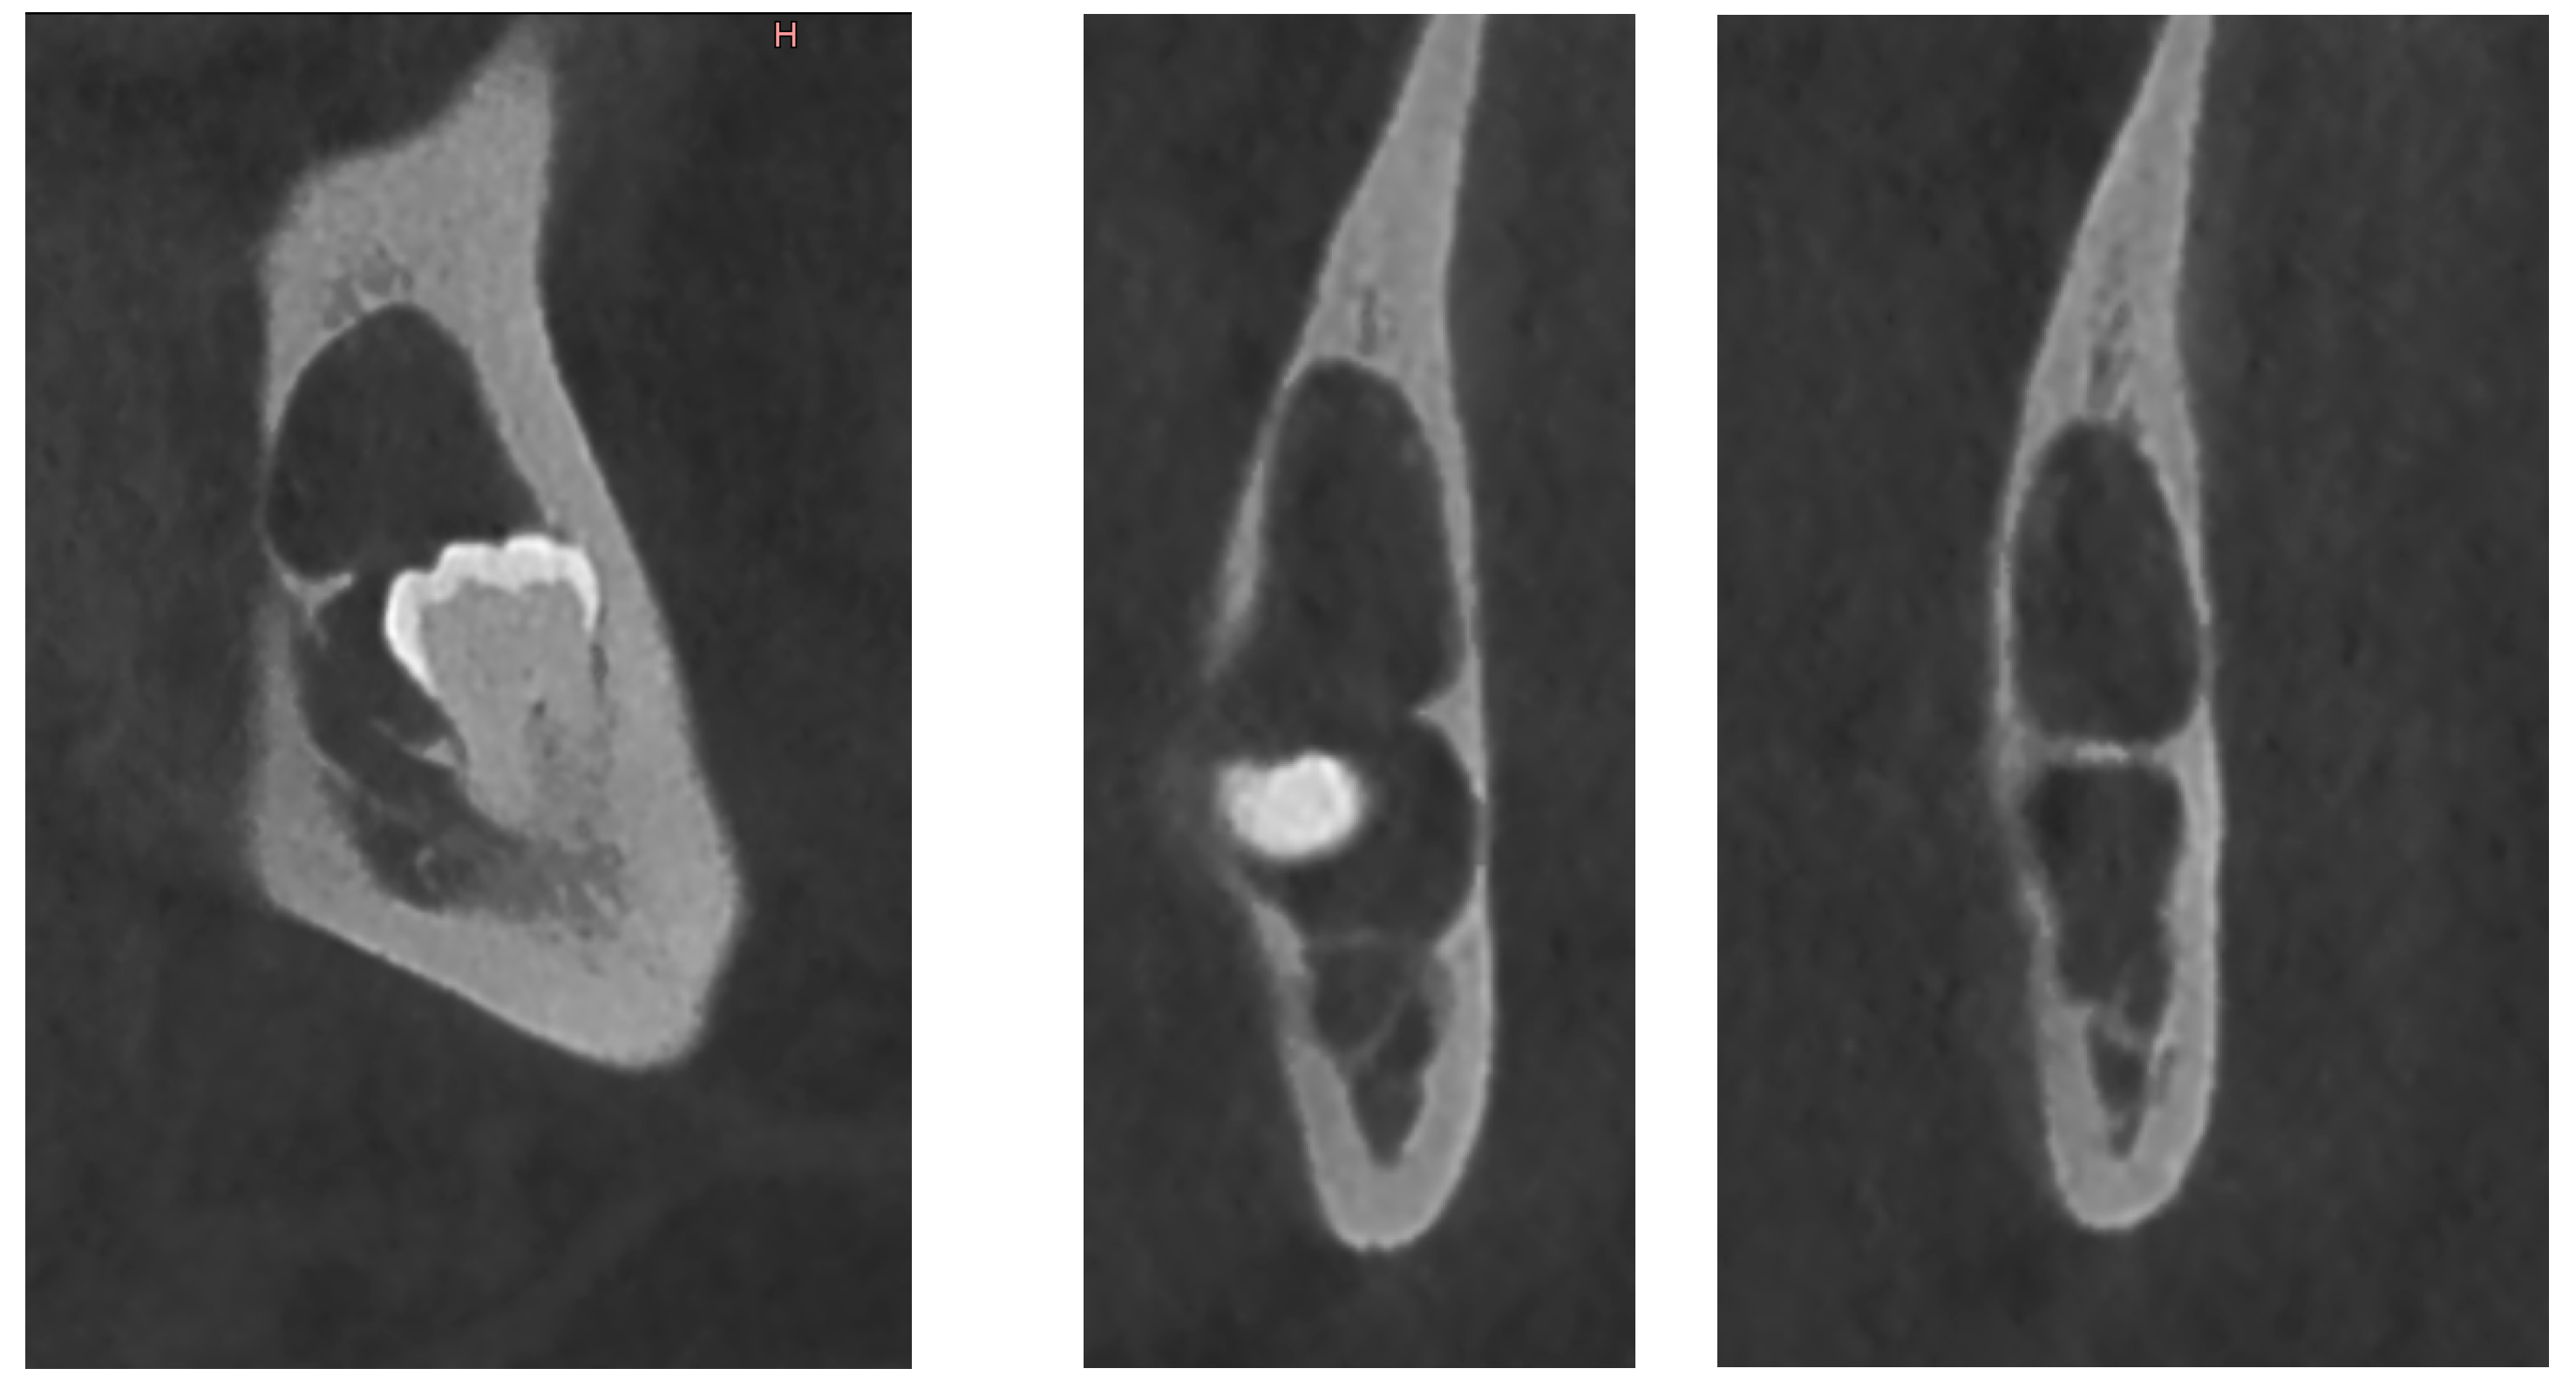

On CBCT X-ray, the distal root of the impacted tooth #38 was in contact with the upper wall of the left IAC, generating a discreet deformation of the canal (Figure 11). The cyst showing a multilocular aspect was located adjacent to the crown of tooth #38 and seemed to be attached to the tooth neck. The lesion extending slightly to the ascending branch of the mandible measured 17 mm in height, 21 mm in length and 10 mm in width. In its caudal part, the lesion was in contact with the upper wall of the IAC over about 13 mm. The wall was thinned but with little impact on its internal diameter. The vestibular and lingual cortex were also strongly thinned focally. There was no periosteal reaction or fracture at the mandibular angle. On the bases of these radiological findings, the differential diagnosis included DC, ameloblastoma, and odontogenic keratocyst.

Figure 11.

CBCT X-ray of case #4.